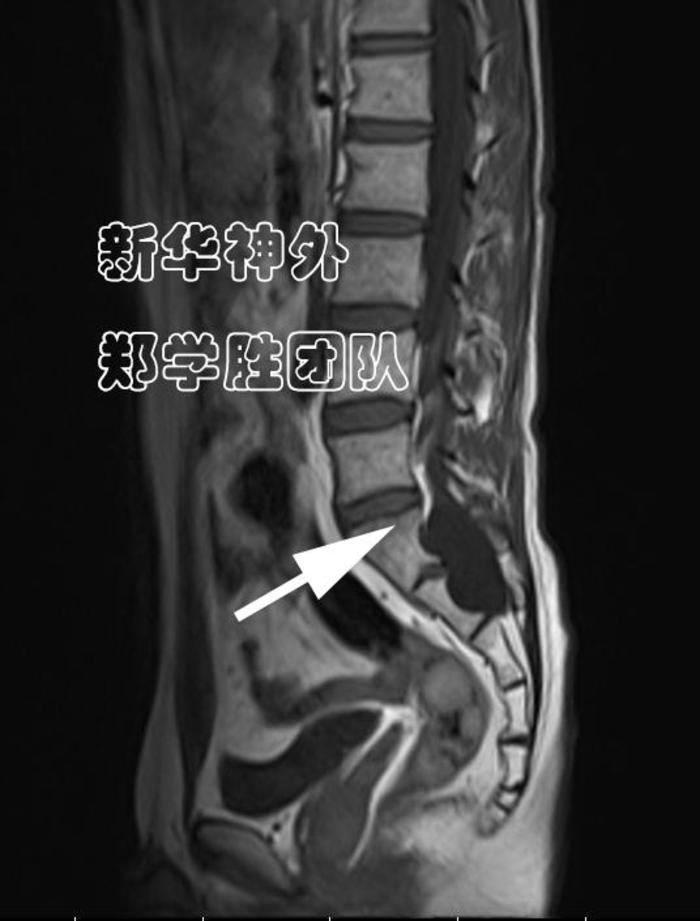

术前MRI显示:8cm巨大腰骶管囊肿;

水往低处流,难道漏口在腰5上段吗?

经过仔细读片,郑学胜主任判断,骶管囊肿漏口很可能在腰5骶1间隙(箭头所指),而不是在腰5上段。